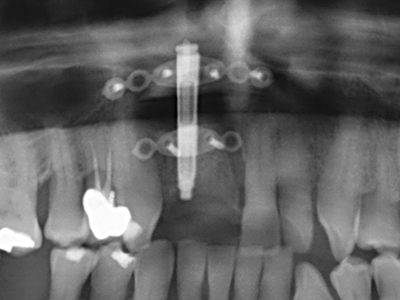

Fig. 1: Preparation of a bone cover with the Piezomed (W&H Salzburg, Austria).

Fig. 11: The postoperative panoramic image shows the vertical augmentation and sinus floor elevation.

Preparation of the lateral window during an external sinus floor elevation is challenging, particularly for implantologists with little surgical experience. Removal of the bone cover of the sinus without injuring the underlying Schneiderian membrane is only part of the operation – after establishing an adequate access, the membranous lining of the sinus must be carefully mobilized to make space for the augmentation materials or the implants. Piezosurgery is useful for this indication in two ways: diamond-coated instruments can be used for selective bone ablation and the underlying mucous membrane remains intact when the procedure is done carefully. The ultrasonic frequencies also enable detachment of the mucous membrane without complications – the frequencies are transmitted into the space between the mucous membrane and sinus floor by special blunt attachments (Cassetta, Ricci et al. 2012, Pereira, Gealh et al. 2014) (Rickert, Vissink et al. 2013). As a result, it is not surprising that current reviews of external sinus floor elevation positively evaluate the use of piezoelectric devices as well as the use of roughened implant surfaces and bone replacement materials (Wallace, Tarnow et al. 2012).